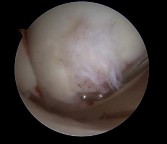

Which image seen during arthroscopic treatment is most likely associated with this patient’s condition?

An otherwise healthy 31-year-old man has had right knee pain for the past 9 months. His former physician

administered a cortisone injection and ordered 6 months of physical therapy. The patient later had an arthroscopy with debridement of the right knee by another physician and completed another course of physical therapy. The patient received minimal relief from these treatments and still is not able to walk longer distances or go on hikes. On examination, he is a healthy appearing male with a body mass index of 24 kg/m2. He has a small effusion, minimal quadriceps atrophy, no tenderness about the knee, full range of motion, stable to varus and valgus stress at 30° of flexion, a grade 1 Lachman test, and a normal posterior drawer. Figures 1 through 4 are his arthroscopic views, radiograph and MRI scan from his prior surgical procedure. What is the next most appropriate step in treatment?